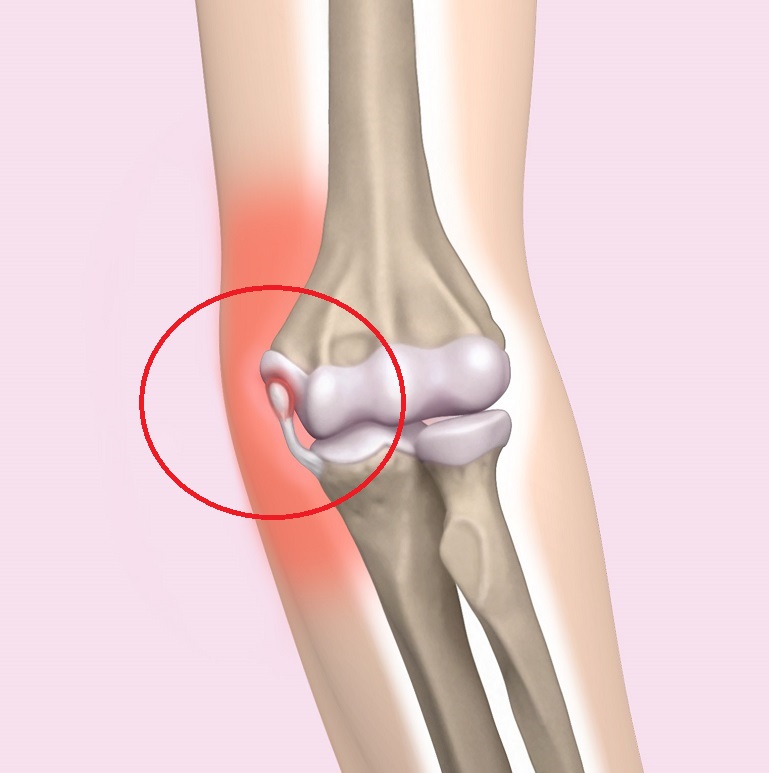

野球肘は名前のごとく、野球によるスローイング動作、特に成長期の投手に多く発生するオーバーユース(使いすぎ)に起因し、投球側の肘の①内側(図1)、②外側(写真1)、③肘頭(写真2)に発生する投球時の疼痛が主症状であるスポーツ障害です。徐々に発症する場合が多く、慢性化しやすいため肘の疼痛が出現したら注意を要します。投球動作の加速期(acceleration)は肘関節屈曲、外反、前腕回外位をとります。内側型は肘の内側部が投球動作時に回内屈曲筋によって牽引力が加わり、回内筋群や内側側副靱帯、尺骨神経がストレッチされ、内側に微細損傷が発生します。重症例では上腕骨内側上顆〈じょうか〉骨が牽引力によって剥離骨折を起こします。外側型は逆に肘外側にある上腕骨小頭や橈骨〈とうこつ〉頭に圧迫力が加わり、骨の壊死〈えし〉、欠損、遊離体などの離断性骨軟骨炎が発生します。後方型は減速期(follow-through)に肘伸展位で、尺骨肘頭に牽引力が加わり剥離や疲労骨折などの変化をきたします。

図1 内側型:上腕骨内側上顆の離開